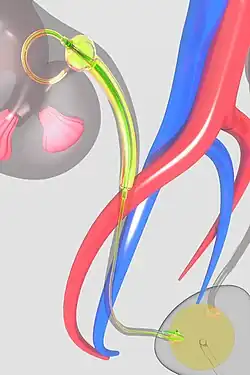

Sketch of an ureteric balloon catheter placed in the ureter. | |

A ureteric balloon catheter is a balloon catheter intended for treating strictures of the ureter. In fact it is a double J stent on which a balloon is mounted. It is connected to a delivery device (pusher) to introduce it from the bladder into the ureter. The system comprises a non-return valve device, and a pusher with a stylet and two ports.

The side port is for injecting contrast agent to inflate the balloon, while the straight port is for the guidewire. The catheter has a relatively large-diameter central lumen and a shaft of 2 mm (6 Fr.). The balloon is in two sections: a long narrow section or shaft and a larger cranial bulb. The larger cranial bulb prevents distal migration, while the longer narrow section maintains the increased diameter of a predilated stricture in the ureter section.